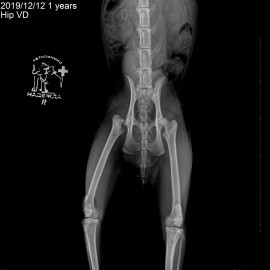

Наш пациент из города Котлас, кот по кличке Кузьма. Первый раз обратились в нашу клинику с жалобами на хромоту на заднюю левую лапу в течение 2 недель. Был проведен осмотр с проведением рентгенологического исследования (снимок 1). Был поставлен диагноз: перелом шейки правого бедра. Была проведена операция - резекционная артропластика правого тазобедренного сустава (снимок 2).